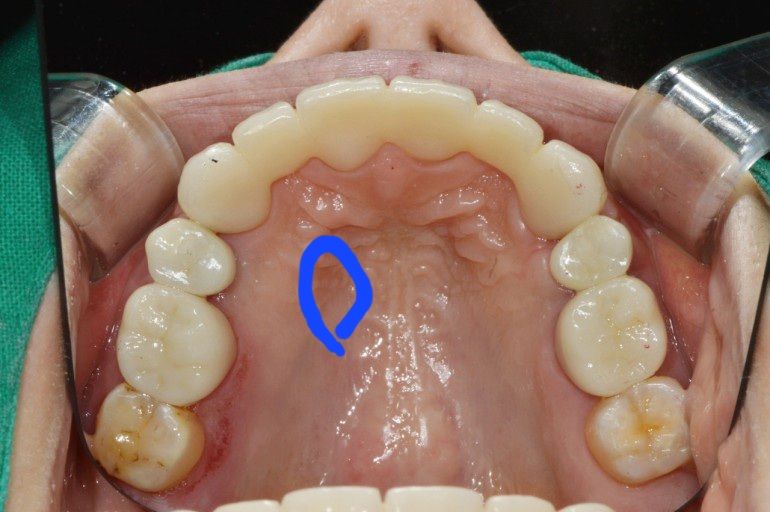

오른쪽 입천장에 혀로 건드리면 아프진 않지만 묵직한 느낌이 있고 치아 뿌리쪽이 약간 욱신거립니다.

혀로 느껴보면 왼쪽천장보다 약간 부은 느낌이 있습니다.

사진은 제 입 안이 아닌 설명을 위한 사진입니다.

• 1번 째 사진